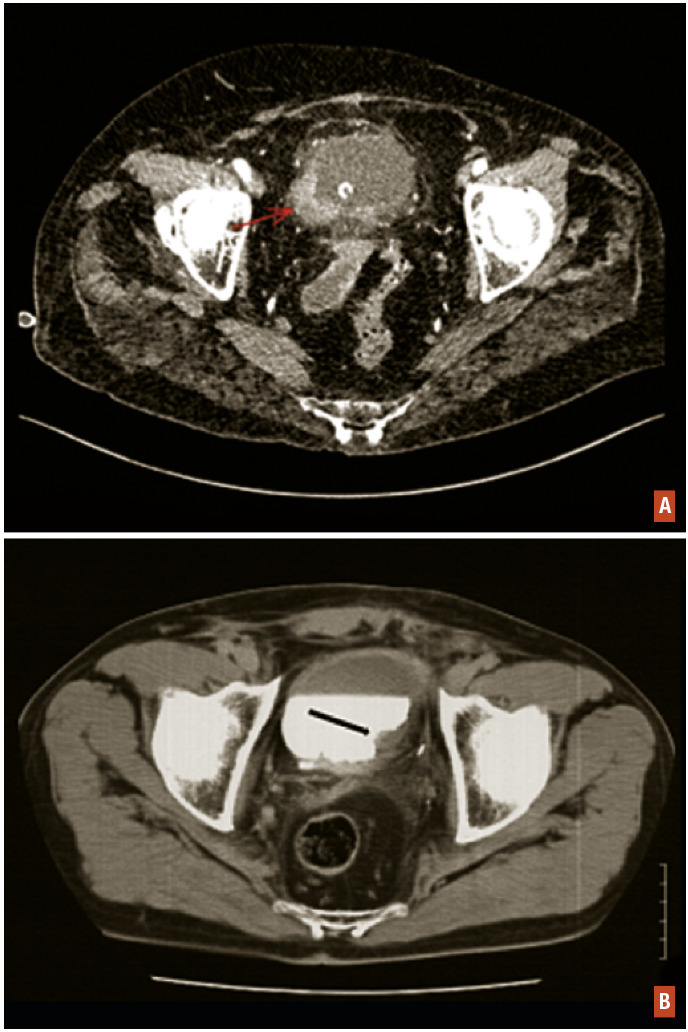

Uro-TDM

L’uro-TDM est une tomodensitométrie abdomino-pelvienne avec et sans injection de produit de contraste associée à une acquisition en temps tardif permettant une exploration de la voie excrétrice dans sa totalité. Elle a une sensibilité supérieure à l’échographie vésicale pour le diagnostic de tumeur urothéliale, y compris de petite taille. Elle permet d’apprécier le retentissement sur le haut appareil et la découverte de lésions synchrones, ainsi que l’extension loco-régionale et ganglionnaire (fig. 2).